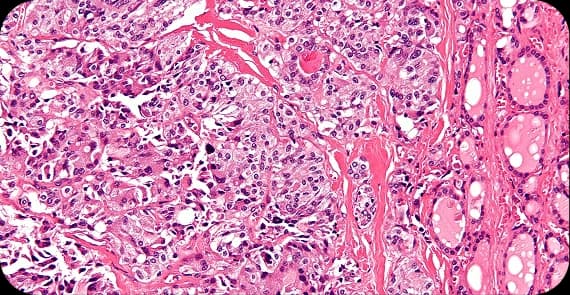

Thyroid cancer treatment depends on tumour type, stage, and overall health.

Common thyroid cancer treatments include:

Surgery: Removes part or all of the thyroid gland

Radioactive iodine therapy: Destroys remaining thyroid tissue or cancer cells after surgery

Hormone therapy: Replaces thyroid hormone and suppresses cancer growth

Chemotherapy: Uses anti-cancer drugs to destroy rapidly dividing cells in advanced cases

Targeted therapy: Focuses on specific genetic or molecular features of cancer cells

Immunotherapy: Stimulates the immune system to recognise and attack cancer cells in selected cases

Many patients respond well to surgery and radioactive iodine therapy, particularly in early stages.